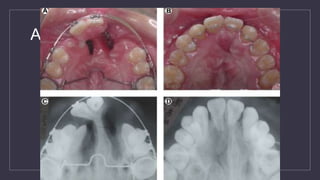

Alveolar Bone Grafting

• Primary Bone Grafting

• Bone graft done at the time of primary cheiloplasty

• Bone graft done during the first 2 years of life

• Bone graft done prior to the eruption of the primary canine

Secondary Bone Grafting

• Done before eruption of the permanent canine

• Usually when the root of the canine is 1/3 to 2/3 formed

• Usually between ages 8-10

• In CLP dental age is usually behind chronological age

Preoperative Cleft Defect Postoperative Bone Graft

Alveolar Bone Grafting PreoperativeCleft Defect Postoperative Bone Graft